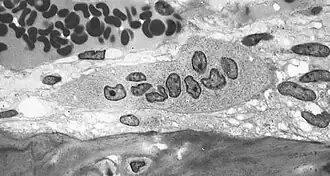

Резорбция костной ткани (разрушение, рассасывание кости, остеолиз) происходит при участии гигантских многоядерных клеток, так называемых остеокластов, которые также имеют большое количество лизосом, митохондрий и вакуолей.

Остеокласт — это основная клетка, участвующая в процессе резорбции кости. При активизации этих клеток у них появляется функциональная зона — «гофрированный край», или «щёточная каёмка». Гофрированный край представляет собой спирально-скрученную мембрану клетки с множественными цитоплазматическими складками, он обращён в сторону развивающегося процесса резорбции и является местом активного окисления тканей.[1]:26-28 Группа остеокластов растворяет минеральный компонент кости, а также гидролизует органический матрикс. Разрушение кости начинается с прикрепления остеокласта к минерализованной костной поверхности «гофрированным краем», через который выделяются гидролитические ферменты и протоны, а также различные интегрины (α₁, αᵥ, β₁, β₃), участвующие в растворении кости.[1]:28 Другие клетки, принимающие участие в резорбции костной ткани — это моноциты и макрофаги. Они взаимодействуют с костной тканью посредством фагоцитоза и хемотаксиса, в большинстве случаев действуя как «уборщики мусора». Помимо фагоцитарной активности продуцируются цитокины (ИЛ-1, ИЛ-1α, ИЛ-1β, ФНО-α и др.) влияющие на активизацию коллагеназ, разрушающих белковый матрикс. Кроме того, моноциты и макрофаги рассматриваются многими учёными как предшественники остеокластов.[1]:31-32 Имеются сведения о влиянии лимфоцитов на резорбцию костной ткани посредством секреции ФНО-β, а также через 1,25-дигидроксивитамин D и ПТГ, к которым лимфоциты имеют рецепторы.[1]:32